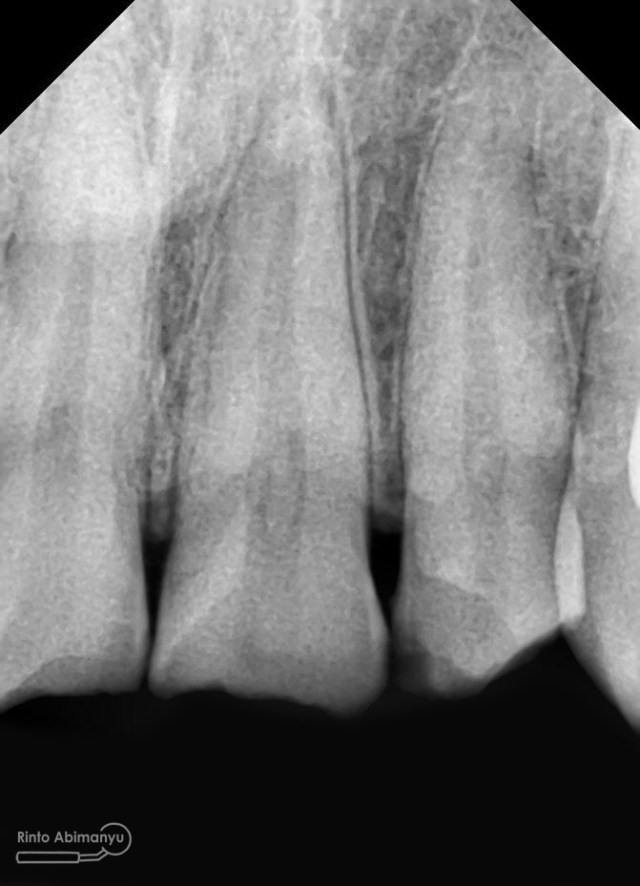

dan ini foto ronsen nya…

Foto radiografis gigi 11 21 22 yang mengalami fraktur

Dari pemeriksaan radiografis lokasi fraktur menyerempet kamar pulpa pada ketiga gigi tersebut… Saya sampaikan kepada pasien bahwa ketiga gigi tersebut memerlukan perawatan saluran akar terlebih dahulu baru kemudian dilanjutkan dengan restorasi indirek… kenapa saya pilih restorasi indirek? Pertimbangannya adalah sisa struktur mahkota gigi yang ada bila hanya di “sambung” dengan restorasi direk dalam jangka panjang rentan mengalami kerusakan, yang kedua pemilihan warna akan lebih maksimal pada kasus ini…. Pasien setuju dengan rencan perawatan yang saya jelaskan…